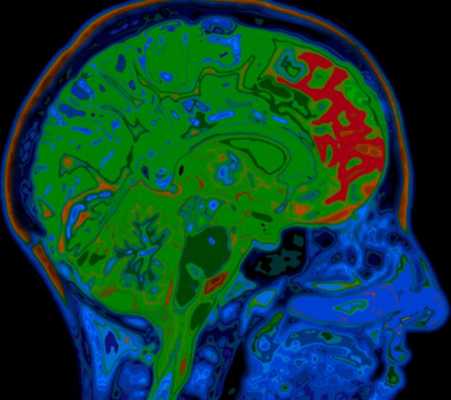

МРТ головного мозга. Демонстрация атрофии и нормы при цветовой обработке.

Под термином “нейродегенеративные заболевания” (НДЗ) определяется большая группа заболеваний преимущественно позднего возраста, для которых характерна медленно прогрессирующая гибель определенных групп нервных клеток и одновременно - постепенно нарастающая атрофия соответствующих отделов головного и/или спинного мозга. В основе развития этих заболеваний лежит нарушение метаболизма и изменение конформации клеточных белков с их последующим накоплением и агрегацией в определенных группах нейронов. При НДЗ страдают преимущественно нейроны и глиальные клетки базальных ганглиев и стволовых структур, вырабатывающие ацетилхолин, дофамин, серотонин.

Болезнь Альцгеймера - прогрессирующее нейродегенеративное заболевание, характеризующееся постепенным развитием деменции. Происхождение заболевания точно неизвестна. Биохимические изменения состоят в снижении активности холин-ацетил-трансферазы коры головного мозга и гиппокампов. Патологические проявления заключаются в образовании специфических амилоидных бляшек, нейрофибриллярных тяжей и реактивном глиозе. Развивается атрофия, захватывающая преимущественно кору вокруг Сильвиевых щелей и гиппокампы, с вторичным расширением желудочков, особенно височных роговЗаболевание впервые описано Alois Alzheimer в 1907 году. Процесс напоминает естественное старение, но резко ускоренное. Начинается с нарушений памяти, затем потерянность, невозможность повседневного самообслуживания, повторяющиеся вопросы. Позже присоединяются глубокие нарушения психики, речи, потеря веса, судороги.

Частота составляет 0,51% для лиц в возрасте 70-74 лет с возрастным прогрессирующим увеличением частоты. Клинические проявления состоят в нарушении памяти, депрессии, поведенческих нарушениях и галлюцинациях. На поздних стадиях к психическим расстройствам добавляется экстрапирамидная симптоматика. Заболевание занимает 4 место по смертности. Диагноз ставится на основании клинического и нейрофизиологического обследования, а также нейровизуализации. Типичные проявления на КТ состоят в диффузной атрофии (особенно,височных долей), вторичном расширении борозд и желудочков. Чувствительность КТ (без измерения объемов) в сравнении с нормальной возрастной группой около 80%, специфичность около 70%. Измерение объемов гиппокампов при выполнении МРТ с тонкими срезами повышает точность до 85%.

МРТ головного мозга служит метода выбора оценки структурных изменений. Атрофические изменения выражены во всём медиобазальном отделе височной доли. Чувствительность и специфичность МРТ при начальной деменции около 80%. Измерение объемов гиппокампов и амигдалы повышает точность до до 85%.